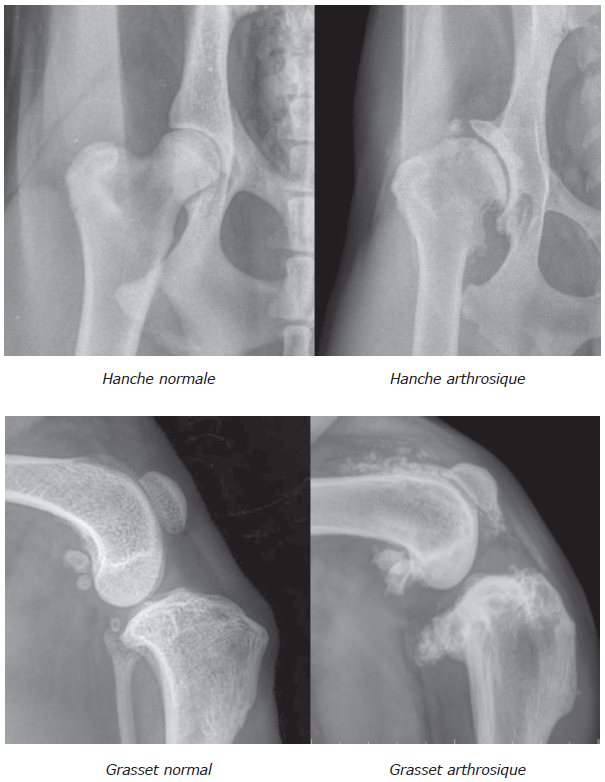

L’anamnèse et l’examen clinique — incluant examen général, examen nerveux, examen orthopédique à distance et examen rapproché — permettent de suspecter une atteinte articulaire. Les radiographies sont souvent suffisantes pour préciser l’affection. Elles permettent de mettre en évidence les lésions d’arthrose (modification de l’os sous chondral, ostéophytes) mais aussi la cause de cette arthrose (malformation, instabilité, etc).